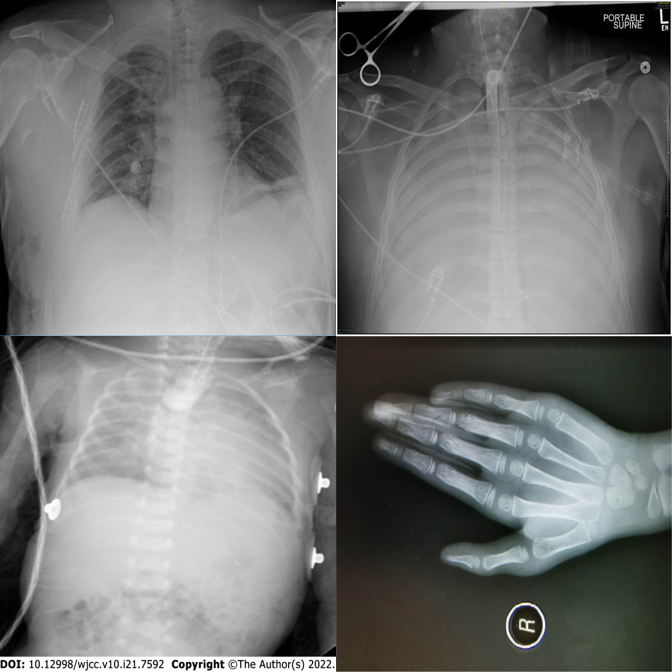

Basic modality mismatches in 2×2 grids. E.g., one MRI scan among CT scans.

Correctly identifies the MRI scan as the modality outlier.

Exhibits strong position bias — always defaults to A regardless of content.

Picks the wrong quadrant despite the correct region.